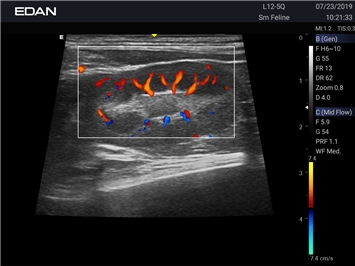

EDAN Acclarix AX2 VET

Ветеринарный ультразвук одним нажатием. Система Acclarix AX2 VET разработана с целью обеспечить бескомпромиссную производительность по доступной цене. Наличие уникальных двойных аккумуляторов в легком корпусе массой 4,5 кг из магниевого сплава позволяет системе Acclarix AX2 VET удовлетворять все потребности ветеринарных исследований, сохранив низкую стоимость.

EDAN Acclarix AX2 VET представляет собой специализированную ветеринарную ультразвуковую систему, сочетающую высокую производительность с доступной ценой. Благодаря продуманной конструкции и передовым технологиям, система обеспечивает качественную диагностику животных различных видов.

Цветовой допплер:

Да

Трехмерная реконструкция ЦДК: